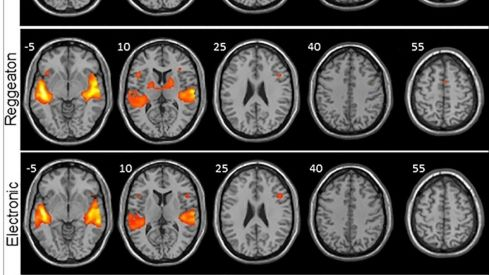

Los investigadores analizaron por un lado anatómicamente el cerebro de cada participante y luego la señal BOLD, que consiste en ver qué áreas del cerebro reclutan oxígeno (que es lo que sucede cuando se activan) y a través de un software se representaron con diferentes colores según se activasen más o menos.La razón por la que se eliminó la letra de los clips musicales de cada estilo es "porque pretendíamos estudiar de la forma más pura posible el procesamiento de la música, y el lenguaje podría (al emplear otras vías neurales) mostrarnos activación cerebral que no es específica de la música".

Y fue el reguetón el que mostró mayor activación en las regiones del cerebro encargadas de procesar los sonidos (áreas auditivas) y de procesar el movimiento (áreas motoras), unas diferencias que resultaron mayores cuando se comparaban con la música clásica.La electrónica también mostró una mayor activación de las regiones motoras, pero significativamente menor en comparación con el reguetón "y lo que más nos llamó la atención fue la activación de una región primitiva del cerebro: los ganglios basales".